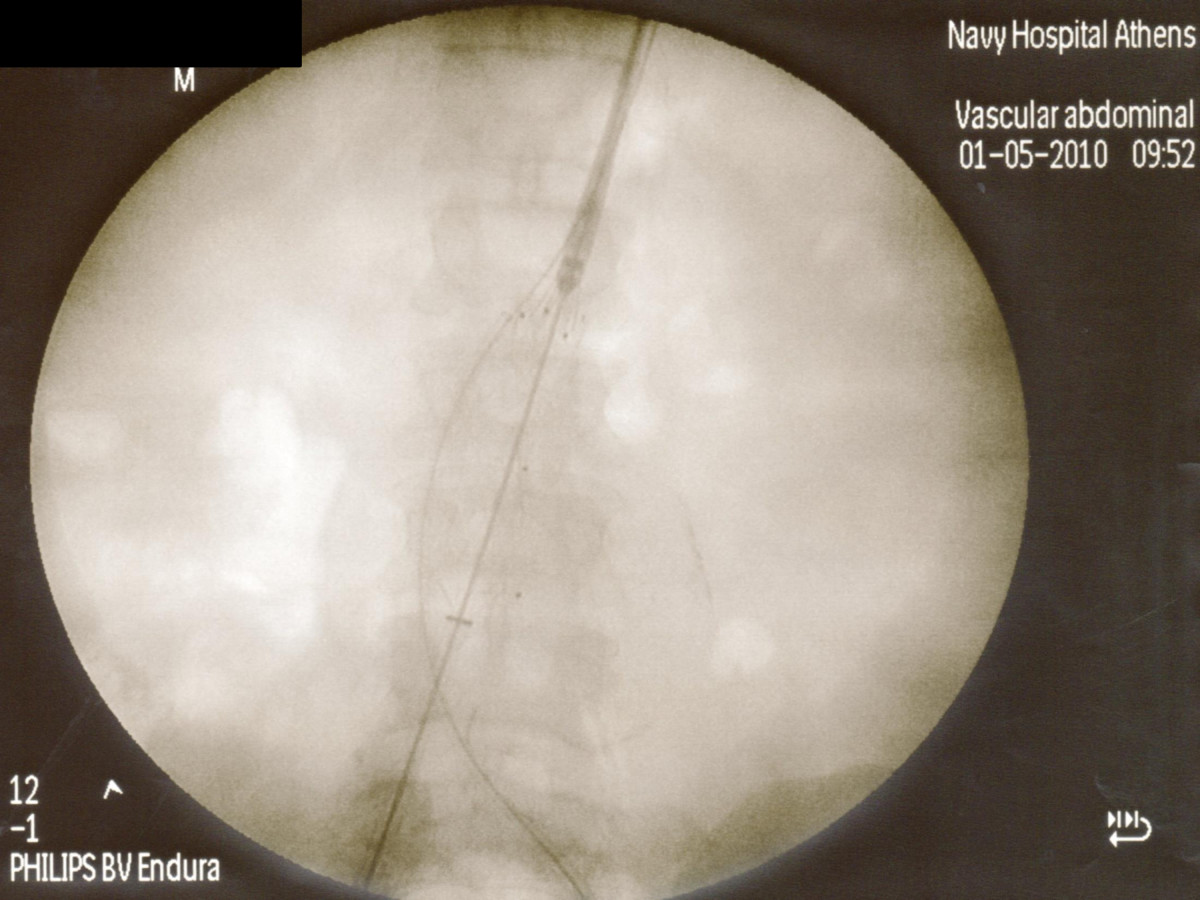

Ενδαγγειακή αποκατάσταση ανευρυσμάτων κοιλιακής αορτής

12ο Πανελλήνιο Συνέδριο Αγγειακής και Ενδαγγειακής Χειρουργικής

2010, Αθήνα